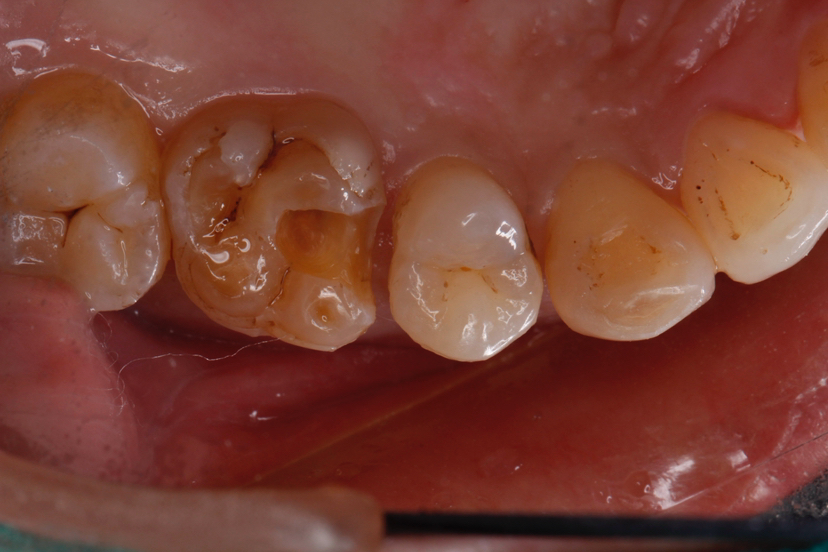

3. 取模或数字化扫描:传统印模或3D口扫,数据发送至技工室制作嵌体。

4. 试戴与粘接:嵌体制作完成后,医生调整并粘固到牙齿上。

5. 抛光与咬合调整:确保修复体与对颌牙咬合舒适。

整个过程通常需要1-2次就诊(数字化嵌体可当天完成)。